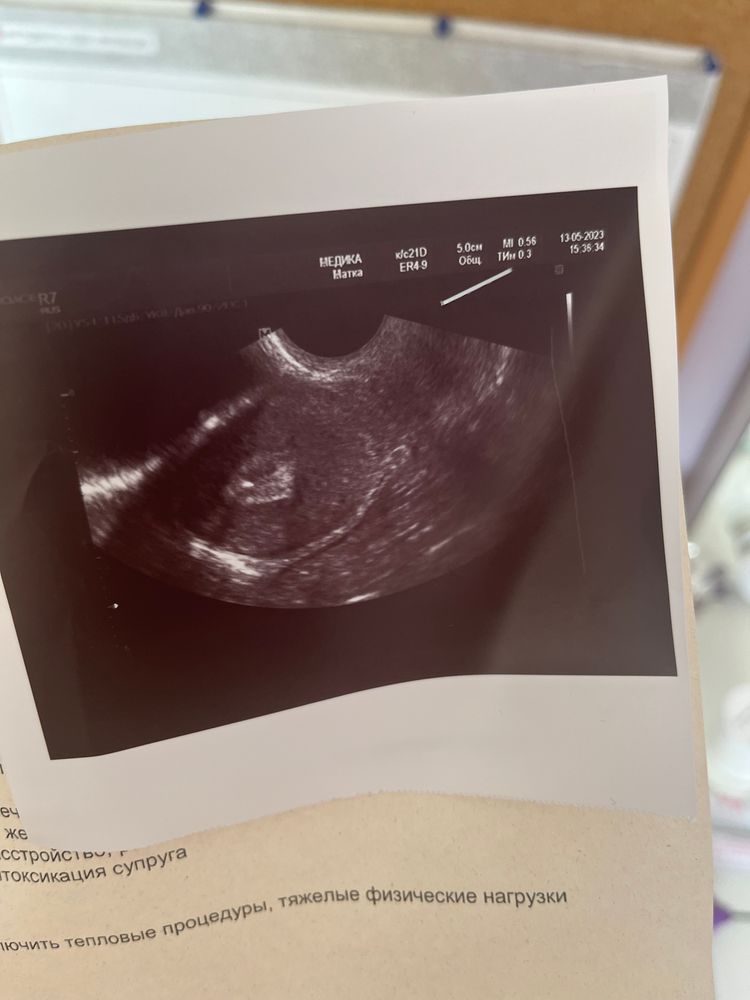

Поздравляю Вас со встречей с малышом!🥰 Пусть крепится за маму и развивается в срок!❤️ А нам портрет не отдали, разрешили только сфотографировать на телефон😁

А сфоткайте пожалуйста нижний лист под фото узи, интересно. Тоже был перенос вчера, но мне ничего кроме утрожестана,папаверина и фолиевой кислоты не назначали.

Елена, мне объясняли, что при полном мочевом он слегка под своим давлением "расправляет" матку, туда легче пройти катетером с эмбриошкой

Олечка, чтоб на узи трансабдоминально матку было хорошо видно, мочевой ее выталкивает ближе к животу)